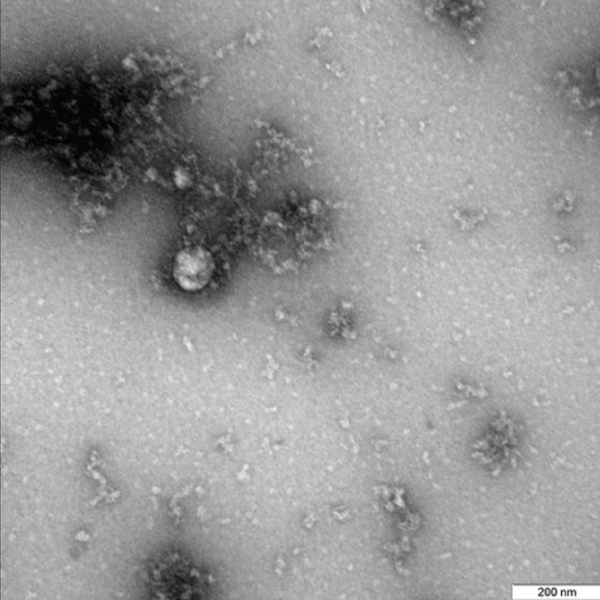

毒株在显微镜下的照片拍摄于使用实验室动物对这种新变种的结构特点、在细胞培养和实验模型中的表现进行深入研究的过程中。

消息称:“俄罗斯联邦消费者权益保护和公益监督局下属的‘矢量’病毒学与生物技术国家科学中心在世界上首次拍摄到于2020年12月从患者身上分离出的新冠病毒英国毒株。”